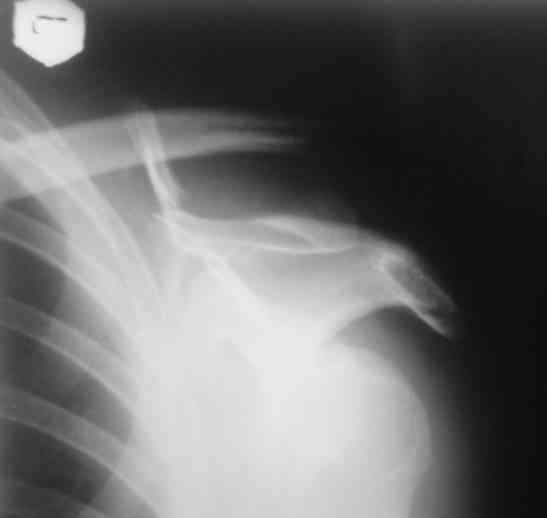

дравствуйте, коллеги. Мужчина 24 лет. Сегодня был прооперирован по Сушко-Илизарову (давно порывался, наконец-то руки дошли :)) На снимке перелом угла лопатки. Довольно крупный размер осколка. Следует ли оперировать такой перелом?Если есть резон оперативного лечения, то каким образом? (рекон. пластина, закрыто пришпилить спицами, винтами). ЭОПа в наличии нет. В области лопатки массивный отек мягких тканей. С уважением, Заднепровский Никита Николаевич

А где там сломанный угол лопатки? Стрелочкой покажите pls?

Посмотрел пациента под рентгеноскопом, определяется изолированный перелом верхнего медиального угла лопатки. Вопрос об операции отпал. Больной машет крылом как пропеллером, пришлось ограничить активность дисциплинирующей "косынкой" ... :))) Отек мягких тканей в области